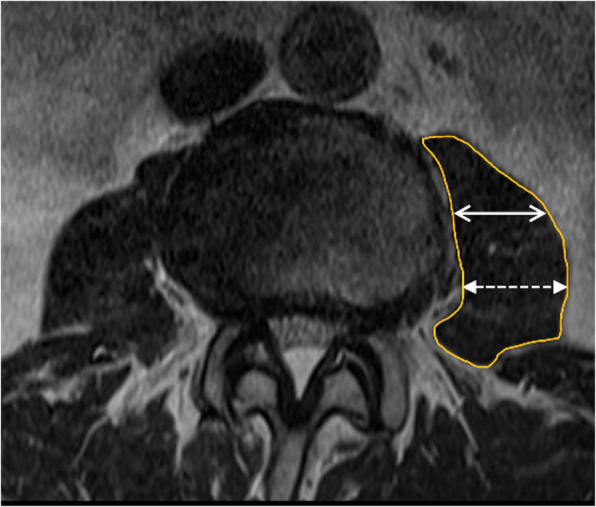

Fig. 2.

Demonstration of manually delineated of the left psoas cross-sectional area (line), the anterior 1/3 of the left psoas muscle (two-headed arrow) and the posterior 1/3 of the left psoas muscle (dotted two-headed arrow)